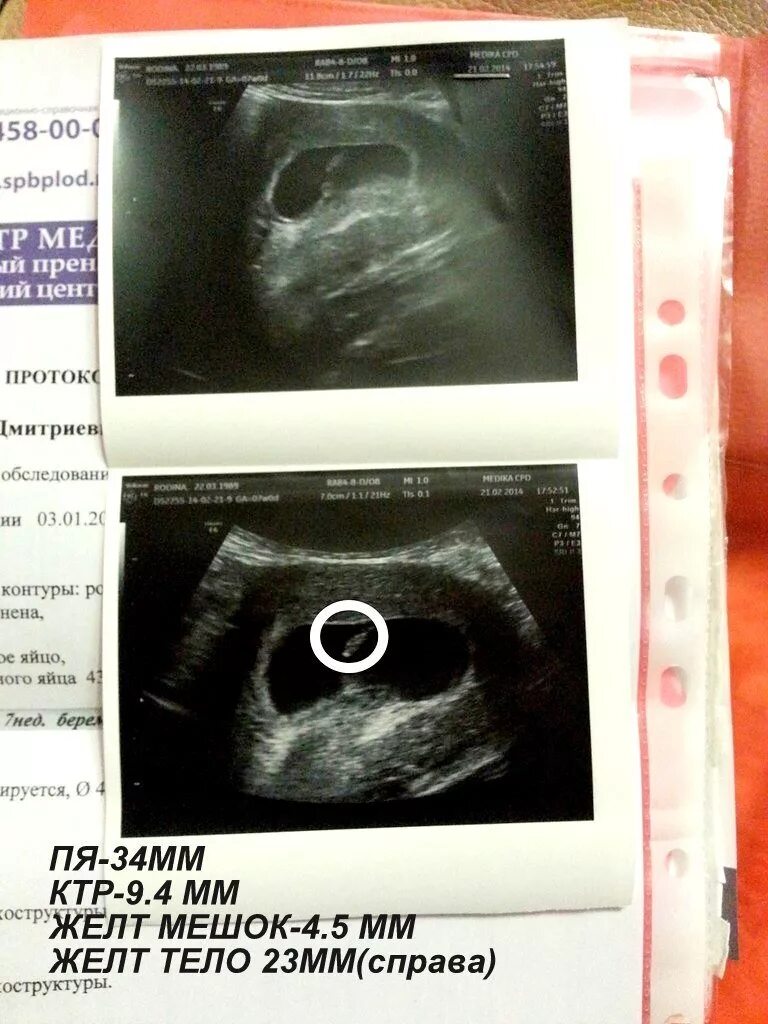

Желточный мешок 2 мм